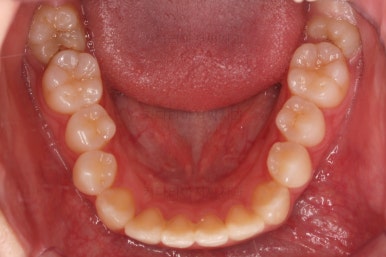

초진 시의 다른 부위들 사진입니다.

약간의 주걱턱 느낌에 약간의 돌출감, 전반적인 치열의 가지런한 느낌은 나쁘진 않았지만 약간의 불량한 교합상태였어요.

다른 부분은 크게 바꾸지 말고 약간의 교합 조절과 어금니 치료에 초점을 맞춰서 교정치료 계획을 잡았습니다.